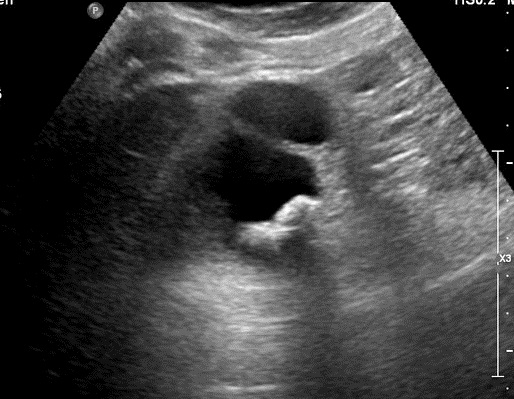

Adenocarcinoma vesiculaire ,

forme infiltrative : Paroi vesiculaire est tres epais,

irreguliee avec un bourgeon intraluminal vesiculaire

. Image echographique percutane en coupe

longitudinale de la vesicule biliaire |